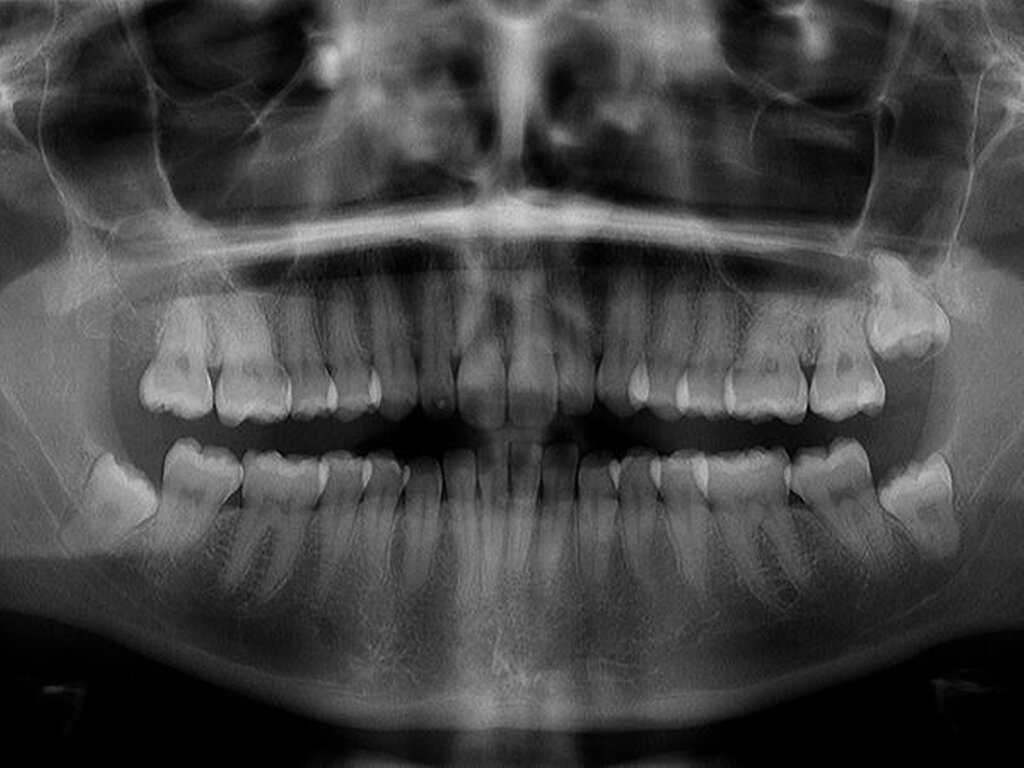

Röntgen (OPG Abb.1): verschattete Kieferhöhle rechts mit extrem verlagertem Zahn 18 direkt infraorbital

In der regionalen Klinik (Winterberg-Krankenhaus Saarbrücken) wurde zusätzlich eine kontrastmittelunterstützte Computertomografie der Nasennebenhöhlen durchgeführt (Abbildungen 2 und 3), die den Befund bestätigte und präzisierte.